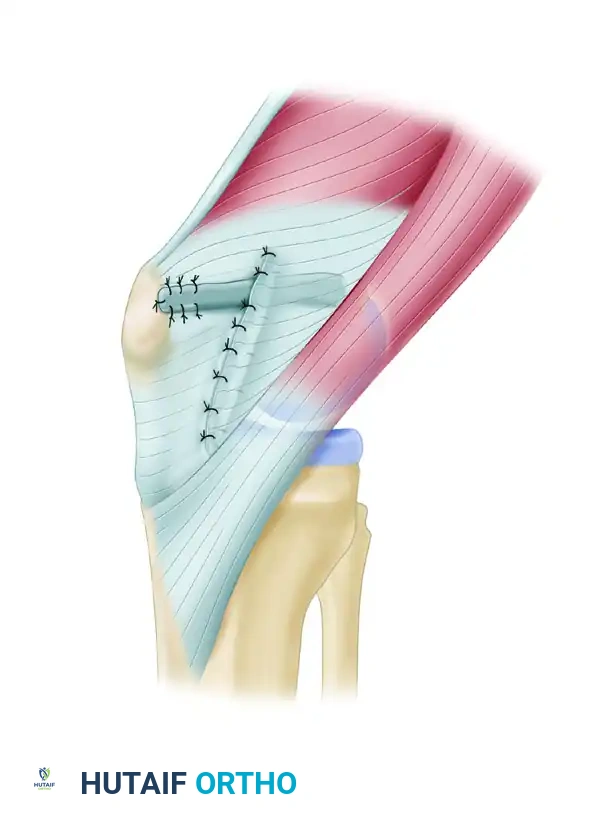

Patellar Preparation and Fixation

- Trough Creation: Use a rongeur or a high-speed burr to create a superficial bony trough along the medial aspect of the patella, localized to the proximal half. Center this trough precisely between the anterior cortex and the posterior articular surface to avoid chondral penetration or anterior cortical blowout.

- Anchor Placement: Flex the knee to 45 degrees to stabilize the patella against the trochlea. Place two double-loaded suture anchors into the trough. Position the first anchor just proximal to the mid-equator of the patella, and the second anchor just distal to the superior pole. Angle the anchors away from the articular surface, ensuring purchase in dense cancellous bone.

Figure 47-15A: Bony trough centered between the anterior cortex and the articular surface of the medial patella.

Graft Passage, Tensioning, and Fixation

- Patellar Fixation: Place the looped end of the graft into the patellar trough. Secure the graft to the patella using one set of paired sutures from each anchor. Preserve the second set of sutures for later retinacular repair.